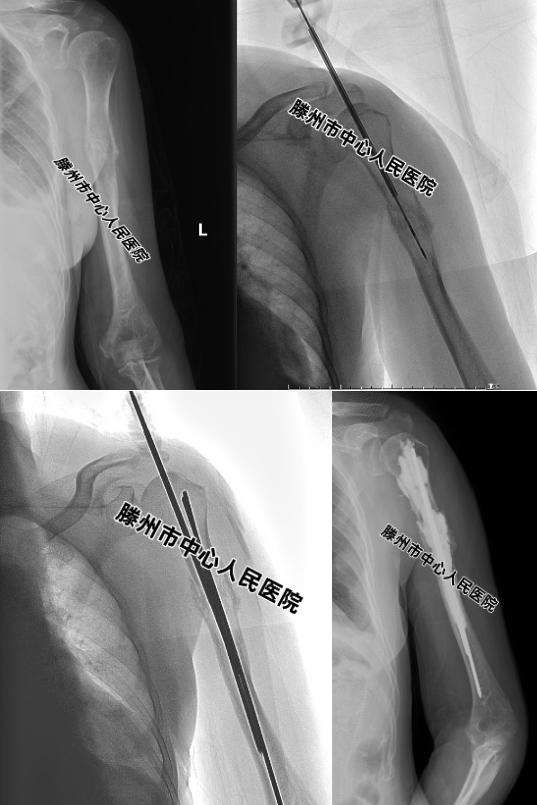

患者,女,62歲,因“咳嗽伴右上肢疼痛1個(gè)月”,在本院診斷為“肺腺癌并右肱骨轉(zhuǎn)移”。先進(jìn)行放療,效果不佳,右上肢疼痛難忍,不能活動(dòng),CT、MRI及拍片檢查發(fā)現(xiàn)右側(cè)肱骨溶骨性轉(zhuǎn)移,骨皮質(zhì)破壞明顯,隨時(shí)都有發(fā)生病理性骨折的風(fēng)險(xiǎn)。

經(jīng)MDT討論,決定采用新的微創(chuàng)技術(shù)進(jìn)行治療。張開賢主任帶領(lǐng)團(tuán)隊(duì),在DSA引導(dǎo)下,先對(duì)病變區(qū)域進(jìn)行微波消融,然后置入2根克氏針,最后再注射15ml骨水泥,術(shù)后第二天疼痛消失?,F(xiàn)患者右上肢活動(dòng)正常,能從事一般家務(wù)勞動(dòng)。